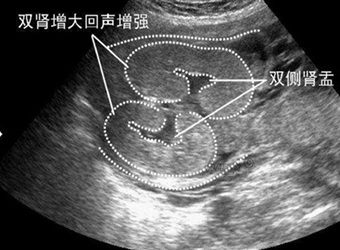

怀孕以后的孕麻麻,几乎每个月都要做不同的检查,做完B超后,很多孕麻麻发现B超单上有双肾未见明显分离的结论,那么双肾未分离是什么意思,更有一些网妈拿双肾…